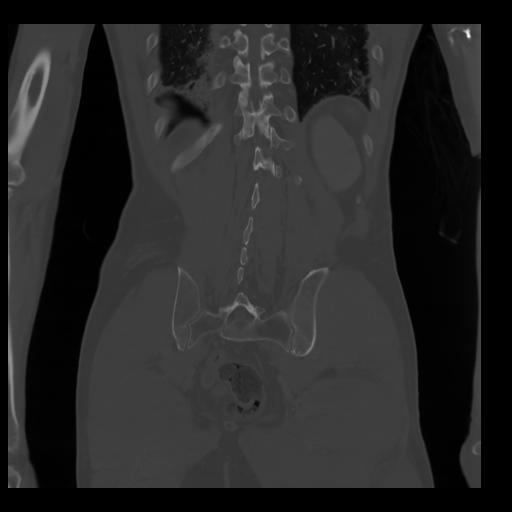

35 CUERPO,CE,Coronal,3.000,CUERPO,Coronal,